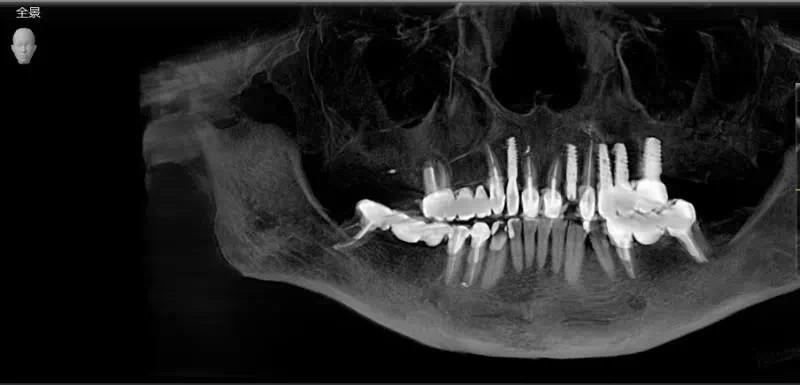

种植牙手术本身就是一个非常复杂且严谨的手术。精准、微创、无痛一个都不能少,海德堡联合口腔UNIC全数字化智能种植体系德国UNIC全数字化智能种植体系到底是什么?将数字化技术与种植理念相结合,保证了种植体精准植入,延长牙齿的使用寿命。